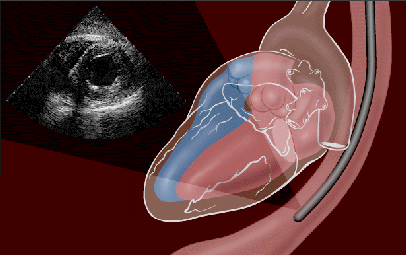

Sonde (rechts im Bild) in der Speiseröhre direkt hinter dem Herzen

Thrombus (Gerinnsel) im linken Herzvorhof